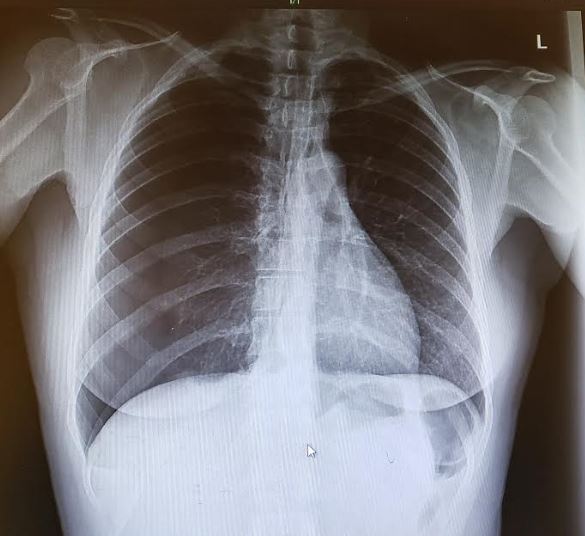

A 39-year-old previously healthy woman presented to an urgent care clinic with chest pain that had been present for the past 4 days.